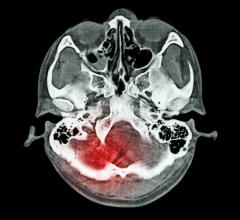

September 15, 2022 — University of Minnesota Twin Cities scientists and engineers have found a way to improve the ...